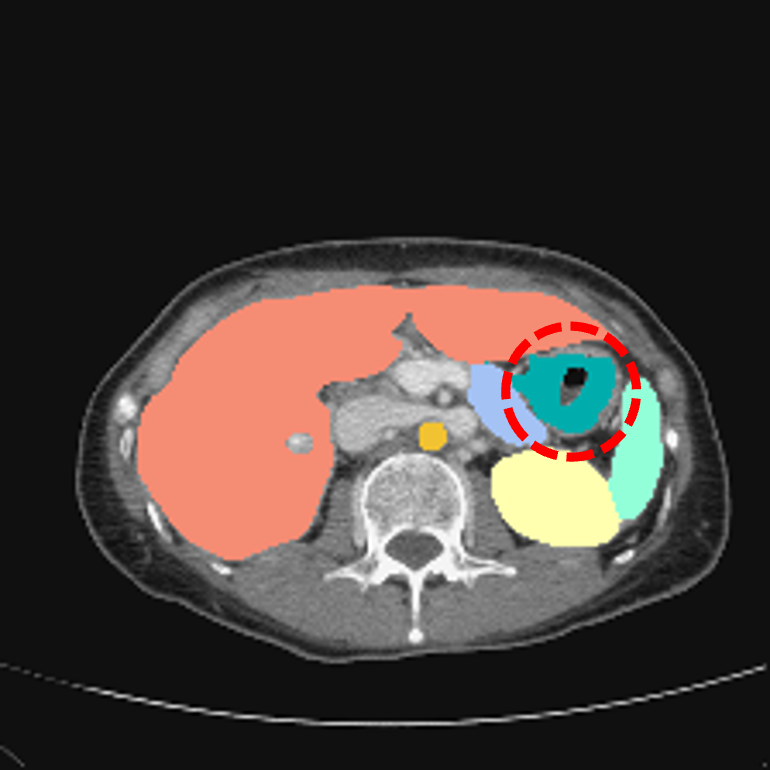

Multi-organ segmentation in CT images: The Synapse multi-organ segmentation dataset [70] contains 30 abdominal CT scans, where 18 (resp. 12) cases are used for training (resp. testing). The goal is to segment 8 abdominal organs. We also conduct evaluations on the AbdomenCT-1K dataset [71] containing more 1000 CT scans from 12 medical centers to benchmark the generalization ability of different methods.

Multi-organ segmentation: For multi-organ segmentation in CT images, Some illustrative results are shown in Fig. 4. Qualitatively, SIKD built on TransUNet [21] accurately segments different organs and preserves their shapes well. The quantitative benchmark on the Synapse multi-organ segmentation dataset is depicted in Tab. 2.

SIKD performs better than the corresponding baseline in terms of both Dice score and HD, implying that SIKD achieves good surface prediction and preserves the shapes better. Specifically, SIKD outperforms the baseline TransUNet by 2.69% Dice score and 8.04 mm HD. Compared with SwinUnet [23], SIKD based on TransUNet achieves an improvement of 1.01% Dice score and 1.89 mm HD. Implementing SIKD with MaxStyle [85] and SAMed [86] also consistently boosts the intra-dataset segmentation performance. The latest 2D D-LKA achieved state-of-the-art (SOTA) performance. Based on this approach, our method improves the Dice score by more than 1%.

We also benchmark the generalization ability of different methods by conducting cross-dataset evaluation on AbdomenCT-1K dataset [71] for the models trained on Synapse multi-organ segmentation dataset [70]. As depicted in Tab. 2, SIKD outperforms all the corresponding baseline models under cross-dataset evaluation. In particular, SIKD built on the baseline of SAUNet [24] improves the baseline model by 11.44% Dice score and 18.48 mm HD. Compared with SAUNet which only incorporates shape information, SIKD achieves 7.17% Dice score and 12.21 mm HD improvement. Building SIKD on SAMed [86] improves the baseline model by 1.6% Dice score and 18.67 mm HD. Based on the SOTA 2D D-LKA method, our approach achieves the best generalization results. This demonstrates that SIKD effectively incorporates the shape-intensity knowledge and generalizes well to images of unseen dataset.